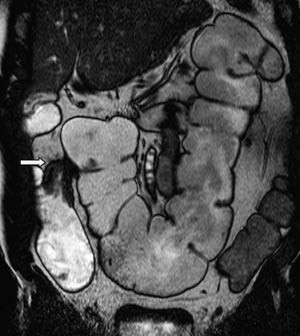

Vår erfaring med MR av tynntarm med oral kontrast er at metoden gir en god utvidelse av ileum. Bulbus duodeni er også ofte væskefylt, men det er vanskeligere å få resten av duodenum og proksimale jejunum optimalt utvidet (fig 3). En annen ulempe med MR av tynntarm med oral kontrast er ventrikkelretensjon (fig 4). Dette hemmer væskefylling av tarmen, og pasientene kan bli kvalme.

Vanlige MR-funn ved Crohns sykdom er fortykket tarmvegg (fig 5). Mer overflatiske forandringer i slimhinnen blir ikke optimalt fremstilt, men dypere ulcuser blir fremstilt, og dette er tegn på aktiv inflammasjon (fig 6). Både fibrose og aktiv inflammasjon i tarmveggen lader opp etter intravenøs kontrast. Det typiske for aktiv inflammasjon er en kraftig og lagdelt kontrastoppladning (fig 7), men den kan også være mer homogen.